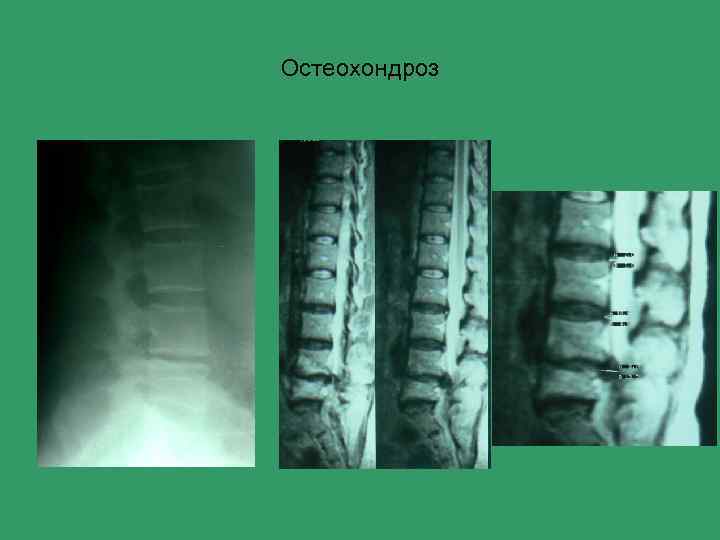

Остеохондроз